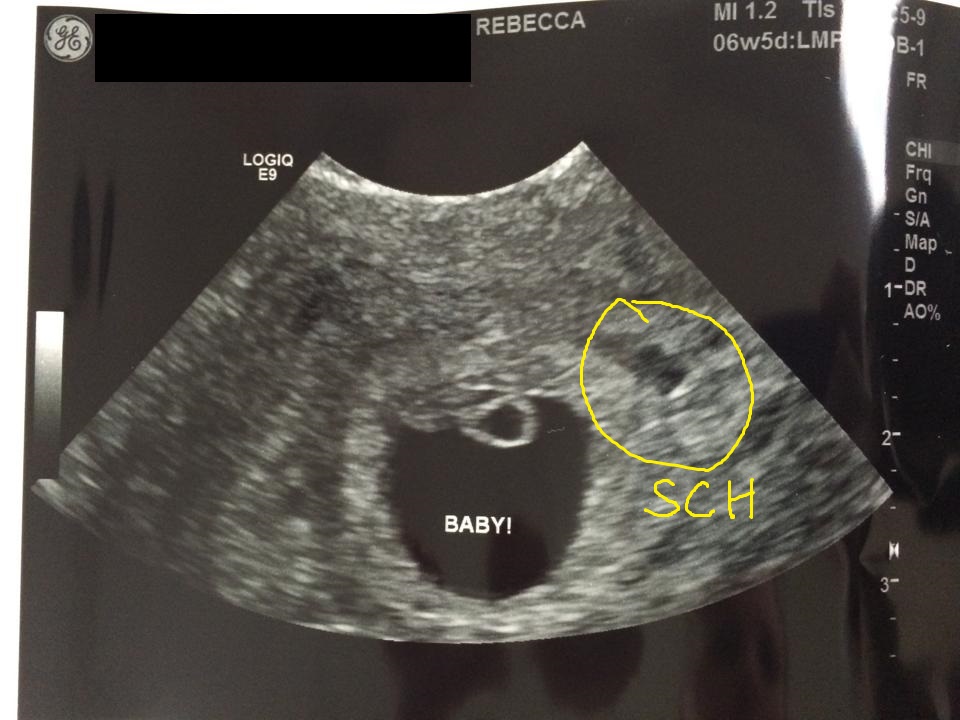

So I had my viability scan yesterday and it was done transvaginally and I'm 6w5d. The other thing is that I got the report this morning which states that the area circled in yellow is a small subchorionic hemorrhage which means that's the side the placenta is forming on. Any thoughts?

Attachment 27629